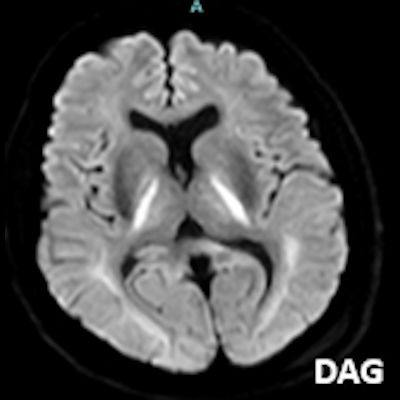

- A) Bilateral serebral kortekste (oklar) ve bazal ganglionlarda (oklar) yaygın DAG hiperintens, ADC hipointens difüzyon kısıtlamaları görülüyor.